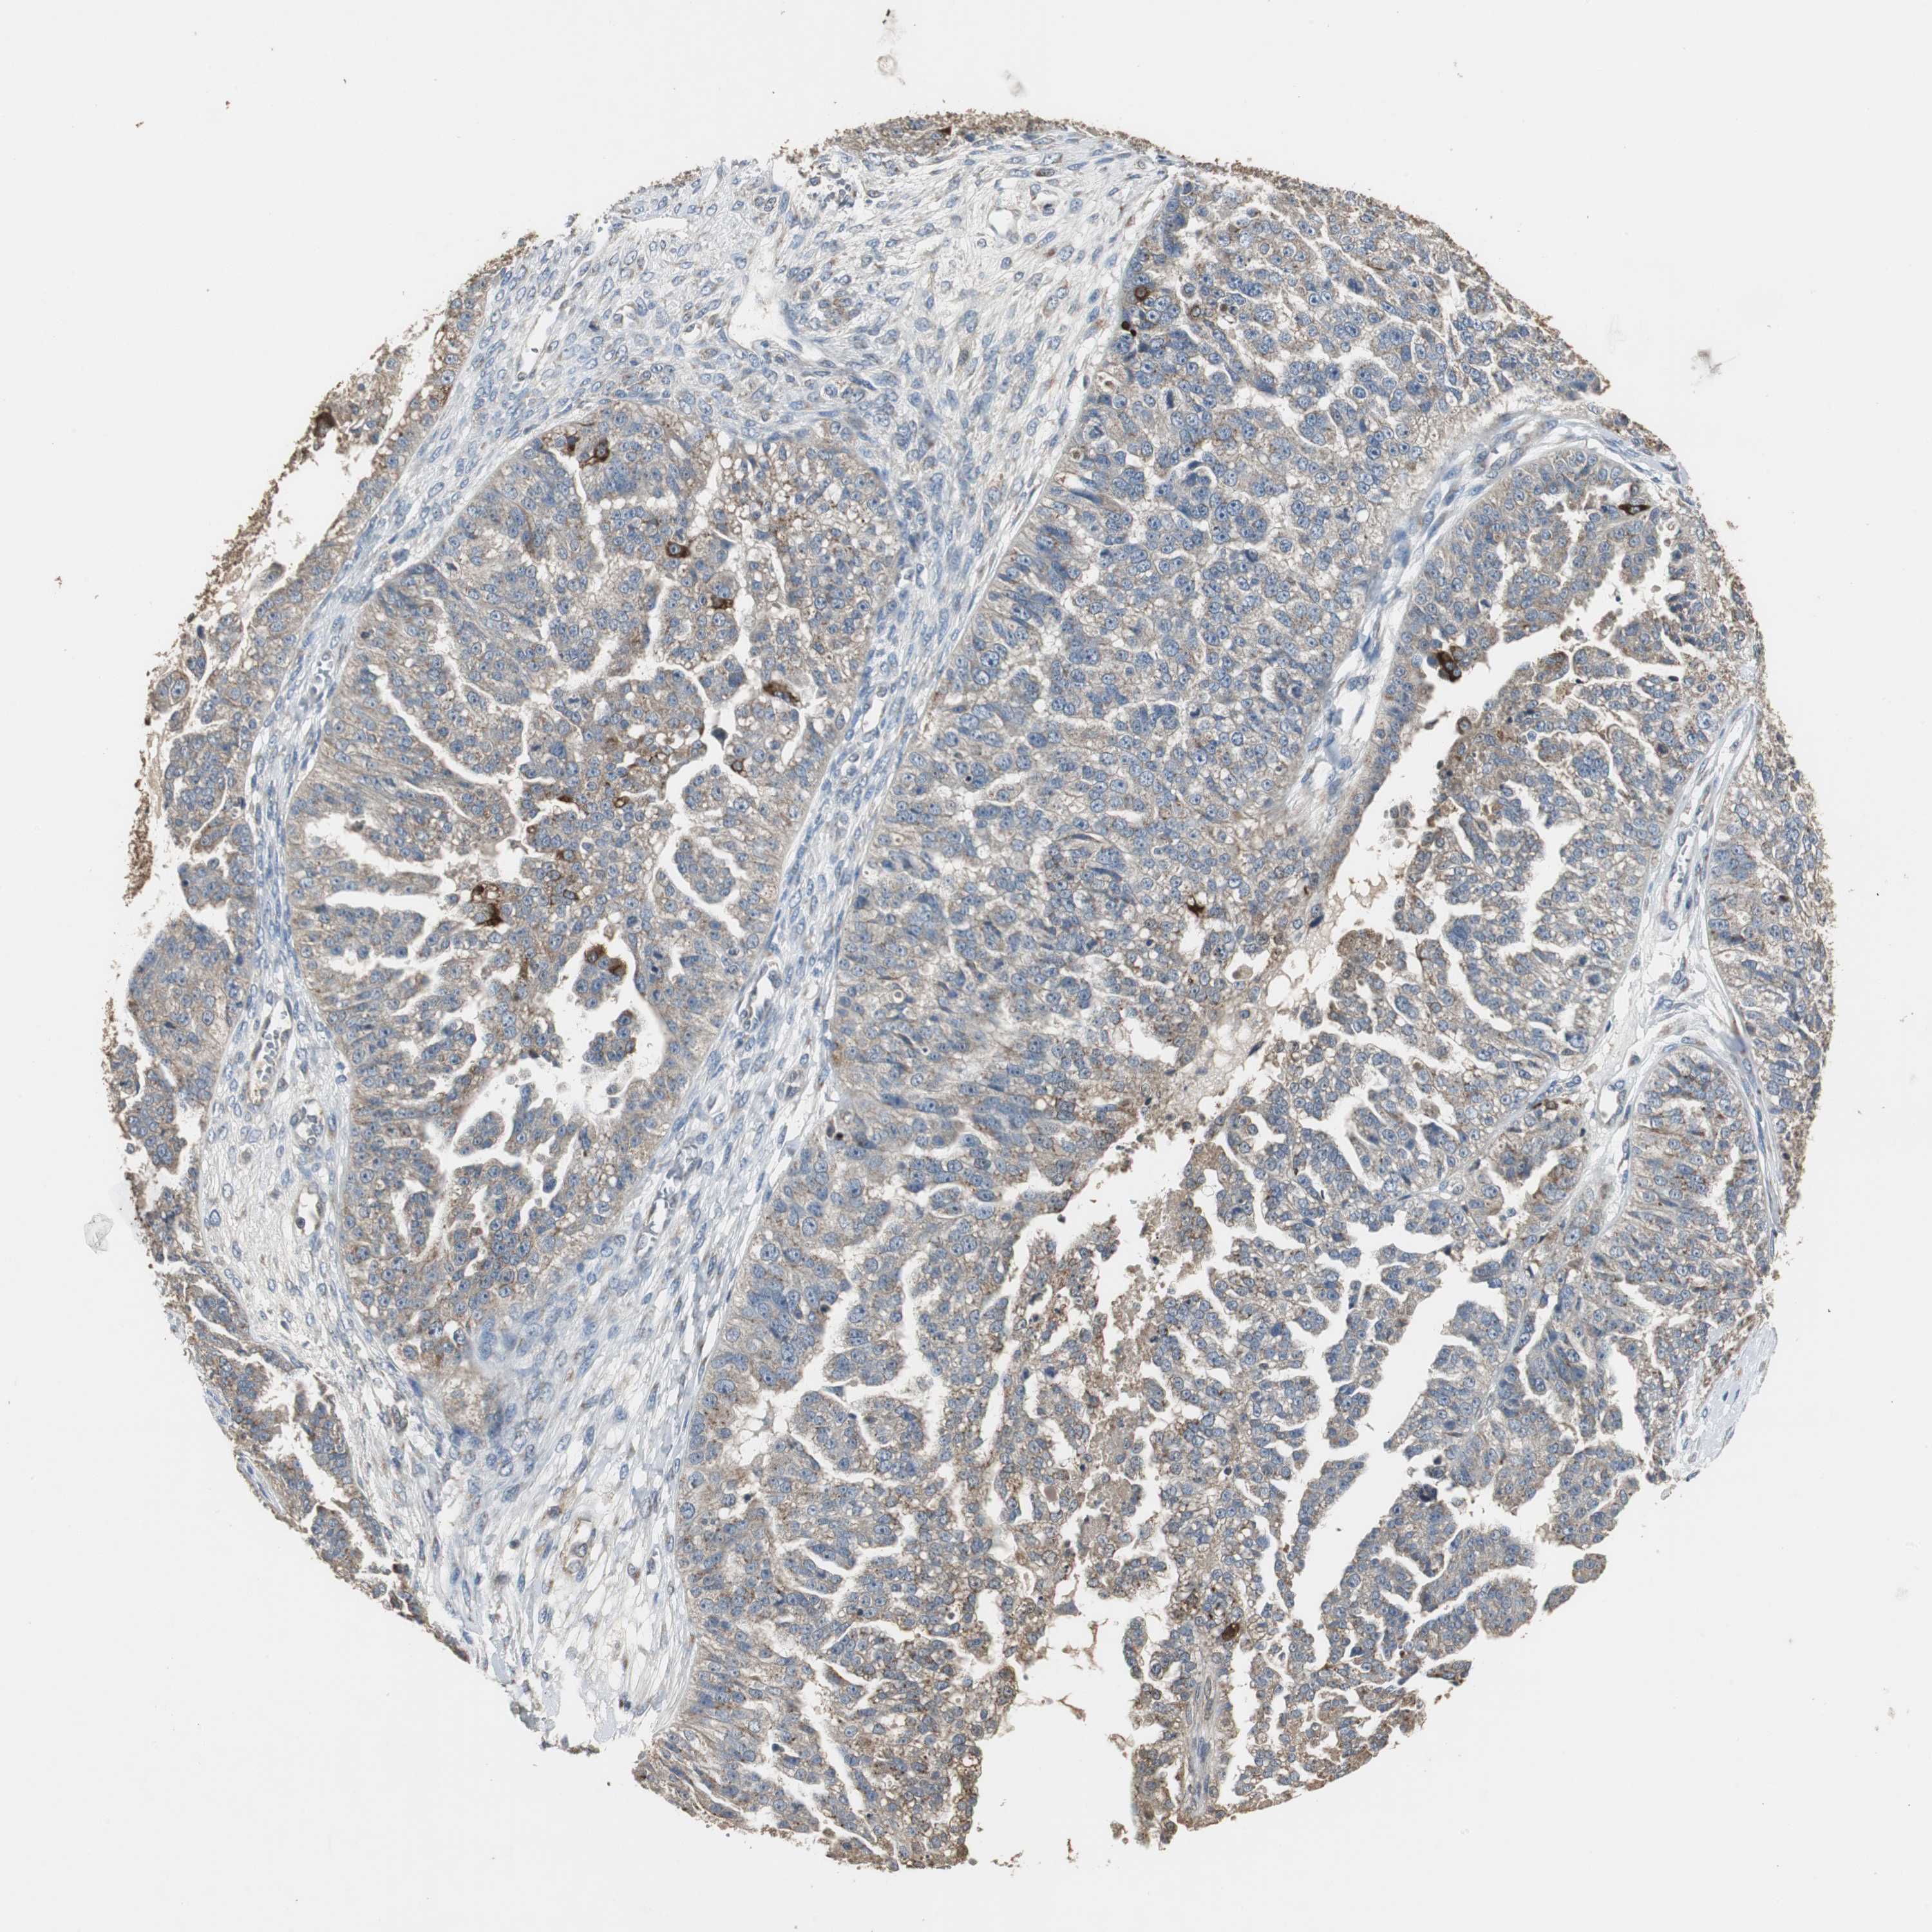

OVARIAN CANCER - Protein expressioni

A mouse-over function shows sample information and annotation data. Click on an image to view it in a full screen mode. Samples can be filtered based on level of antibody staining by selecting one or several of the following categories: high, medium, low and not detected. The assay and annotation is described here.

Note that samples used for immunohistochemistry by the Human Protein Atlas do not correspond to samples in the TCGA dataset.

Antibody stainingi

Antibody staining in the annotated cell types in the current human tissue is reported as not detected, low, medium, or high, based on conventional immunohistochemistry profiling in selected tissues. This score is based on the combination of the staining intensity and fraction of stained cells.

Each image is clickable and will lead to virtual microscopy that enables deeper exploration of all samples and also displays staining intensity scores, fraction scores and subcellular localization as well as patient and tissue information for each sample.

Antibody HPA006514

Staining

High

Medium

Low

Not detected

Intensity

Strong

Moderate

Weak

Negative

Quantity

>75%

75%-25%

<25%

None

Location

Nuclear

Cytoplasmic/membranous

Cytoplasmic/membranous,nuclear

Cystadenocarcinoma, serous, NOS

Carcinoma, endometroid

Carcinoma, NOS

Cystadenocarcinoma, mucinous, NOS